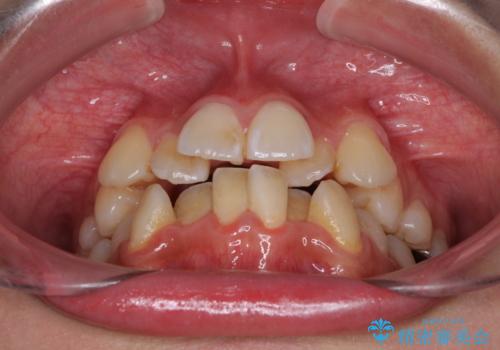

- 上下前歯のデコボコと、それによる磨きづらさを気にして来院された患者様です。

叢生解消のため、上下左右第一小臼歯4本を抜歯し、ワイヤー装置にて矯正治療を行うこととしました。

半年ほどで前歯のデコボコは改善され、汚れの溜まりやすさは解消されました。